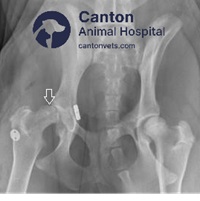

The Toggle Pin Repair involves drilling two holes – one through the femoral head and neck from the third trochanter to the fovea capitis, and the other through the center of the acetabular fossa. The prosthetic ligament, often made of monofilament nylon or braided materials like LigaFiba Suture, is anchored to the medial wall of the acetabulum using a toggle pin and secured to the femoral neck with a knot, suture button, or second toggle pin.